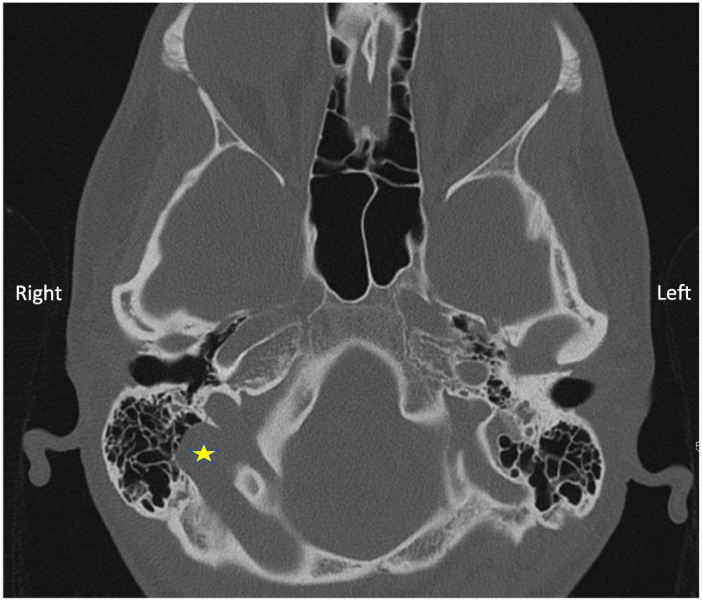

All the routine blood tests including thyroid function tests were normal. MRI brain and internal auditory canals was normal. The CT scan of the petrous temporal bone showed a large high lying right-sided jugular bulb. It also showed dehiscence of right sigmoid plate with herniation of the lateral aspect of the transverse and sigmoid venous sinuses into the mastoid complex (Figure 3 [Fig. 3]).

Figure 3: CT scan showing the right high jugular bulb, dehiscent sigmoid plate with sigmoid sinus herniation into the mastoid (yellow star)